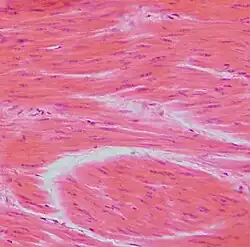

Músculo liso é um tecido muscular de contração involuntária e lenta, composta por células fusiformes mononucleadas.[1]

As células do músculo liso podem também reagir a estímulos vindos de células vizinhas ou a hormonios (vasodilatadores ou vasoconstritores). Nestas células, os canais de cálcio induzem contração. São geralmente organizadas em folha ou em fascículos e são mantidas unidas e em contacto intercitoplasmático por gap junctions (junções de hiato). No estado relaxado tem forma de fuso, têm de 25-50 µm de comprimento e 5 µm de largura.